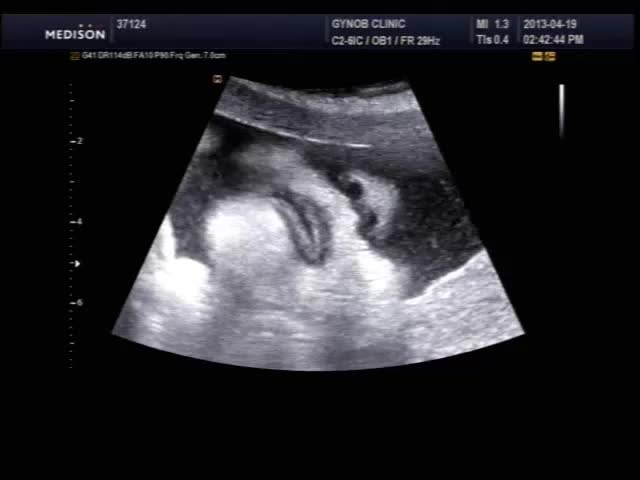

오늘 초음파 보신 산모의 영상인데 태아의 입과 인중 부분이 잘 보이는 편이라 여러분들께 보여드릴 겸, 그리고 설명 드릴 것도 있고 해서 올려 봅니다.

초음파 검사시 태아의 입과 인중을 살펴보는 것은 구순열과 같은 기형이 있는가 보는 목적이며 요즘은 초음파 장비 기술이 발달하여 비교적 쉽게 중기에 진단이 가능합니다.

태아는 뱃속에서도 보고 듣고 먹고 다 할 수 있는데 위 영상을 보시면 태아가 입을 오물거리면서 무언가를 말하는 것도 같지만 사실 말을 하는 것은 아니고 음식을 먹는 운동을 하면서 실제 양수를 삼키는 모습입니다.

뻐끔거리는 입도 잘 보이고 콧구멍도 잘보이고~~ 완전 신기하네요~~!! ^0^

24주 이상되면 다 저런 모습으로 볼 수 있습니다. 물론 아기 자세가 받쳐주어야 하지만....  등록시간 2013-04-19 19:01